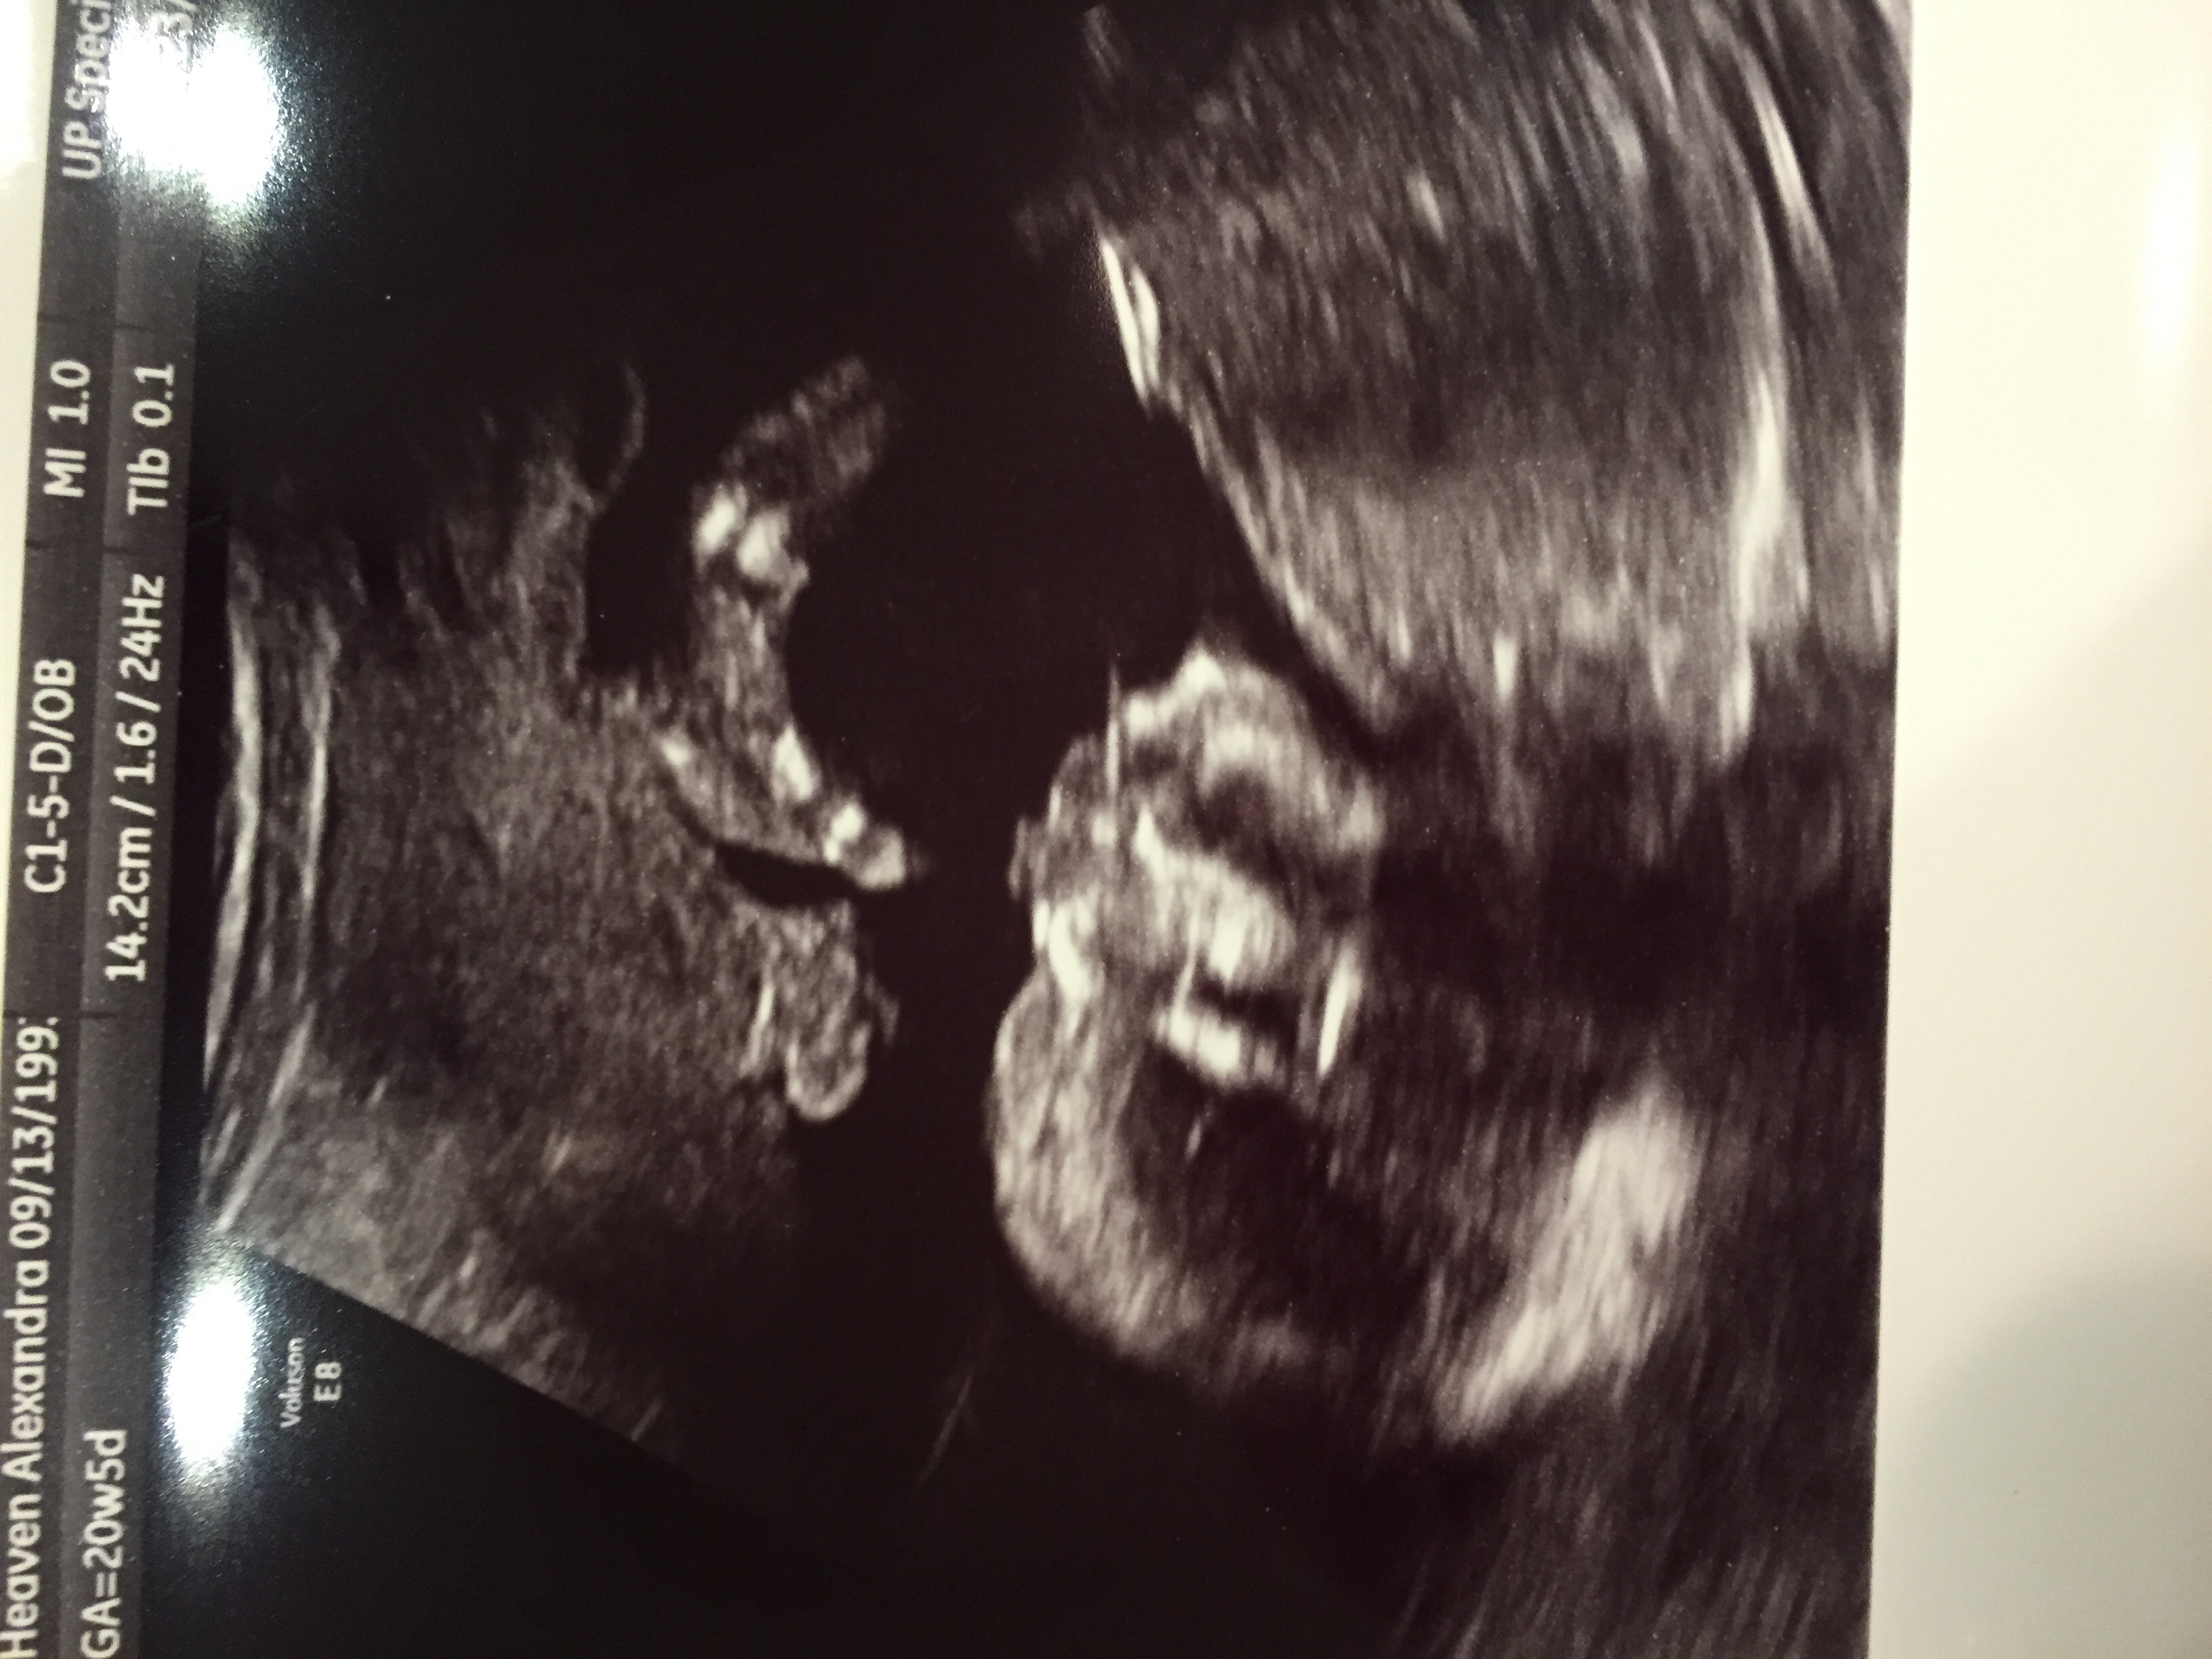

Hi! My name is Alex and I'm new here. I'm 21w5d with my first! I have never been so amazed in my life by everything that is going on, but of course I also have a ton of questions. I don't have any pregnant friends or really anyone I can talk to about things concerning my baby except my hubby (and sometimes they just don't understand.) I am in nursing school full time and would love to make new mama friends!